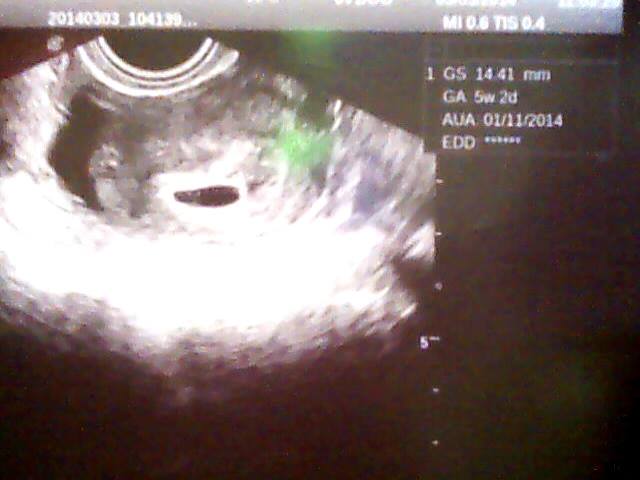

Renčo ted jsem koukala na fotky co mám z utz a v 5+2 jsem měla plodové vejce mělo 14,41mm a taky tam ještě nebyl vidět plod a o týden později už tam bylo vidět embryo jen bez srdíčka a o další týden už i se srdíčkem,takže neplaš...určitě je to vše v pořádku :-)tady přikládám tu fotečku